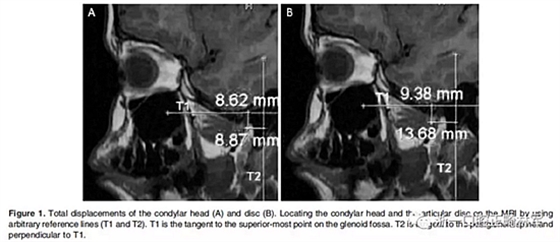

在生理休息位和另外三個(gè)位置獲得了四個(gè)咬合蠟型,這三個(gè)位置是水平前伸0mm時(shí)的HA1,水平前伸5mm時(shí)的HA2以及水平前伸7.5mm時(shí)的HA3。所有三個(gè)位置均保持垂直高度為5mm。病人分別將四個(gè)蠟型咬在嘴里,接受了5次連續(xù)磁共振掃描。外部標(biāo)記的Frankfort水平面保持垂直于掃描臺(tái)。標(biāo)記髁突頭和關(guān)節(jié)盤的位置,并在整個(gè)研究過程中對(duì)它們的位置變化進(jìn)行描繪(Figure 1和2;1Table 1和2)。